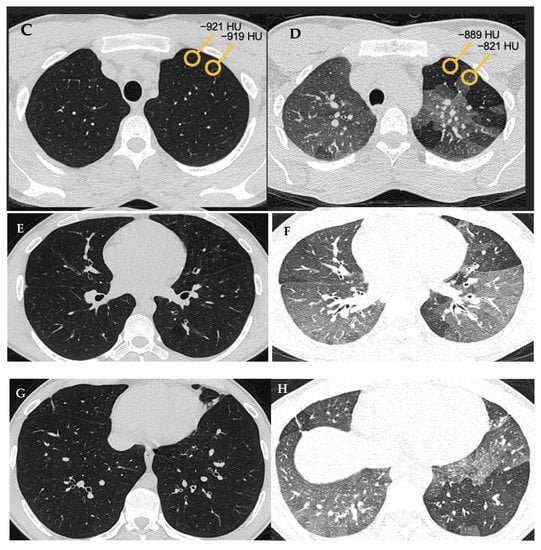

| Typical HP Pattern (Suggests a Diagnosis of HP) | Compatible with HP | Indeterminate for HP |

|---|---|---|

| At least one finding indicative of small airway disease | Not applicable | |

| Air trapping | ||

| Ill-defined <5 mm centrilobular nodules | ||

| At least one finding indicative of parenchymal infiltration | ||

| Mosaic attenuation | Diffuse and subtle GGO | |

| GGOs | Airspace consolidation | |

| Lung cysts | ||

| Distribution of findings | ||

| Craniocaudal: diffuse +/− basal sparing | Craniocaudal: diffuse (variant: lower lobe predominance) | |

| Axial: diffuse | Axial: diffuse (variant: peribronchovascular) | |